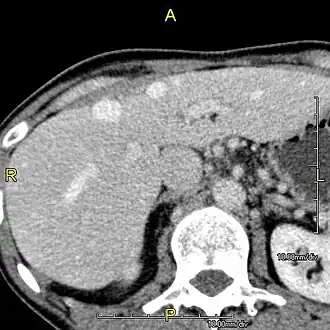

-

Axial CT image showing anomalous hepatic veins coursing on the liver's subcapsular anterior surface[74] -

Maximum intensity projection (MIP) CT image as viewed anteriorly showing the anomalous hepatic veins coursing on the anterior surface of the liver -

Lateral MIP view in the same patient as previous image -

A CT scan in which the liver and portal vein are shown